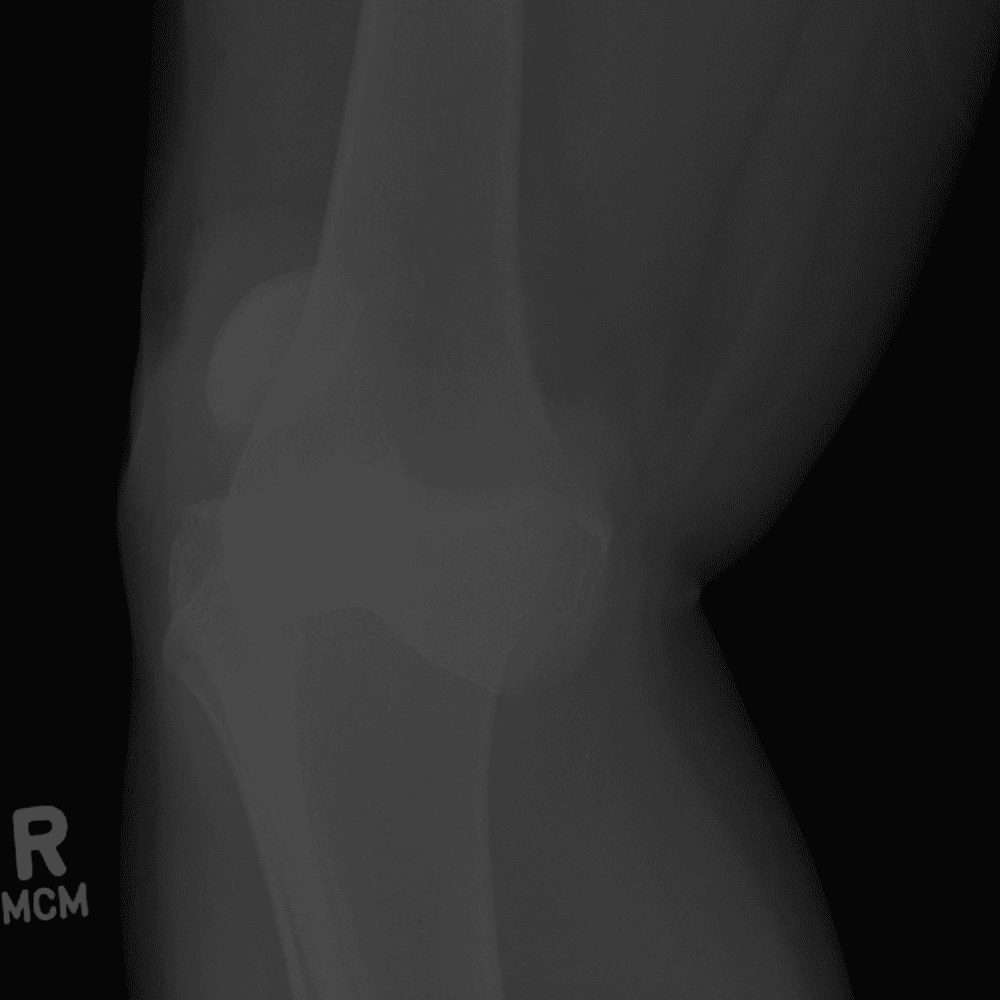

Simula o plantão incluindo casos sutis ou difíceis e alguns normais.